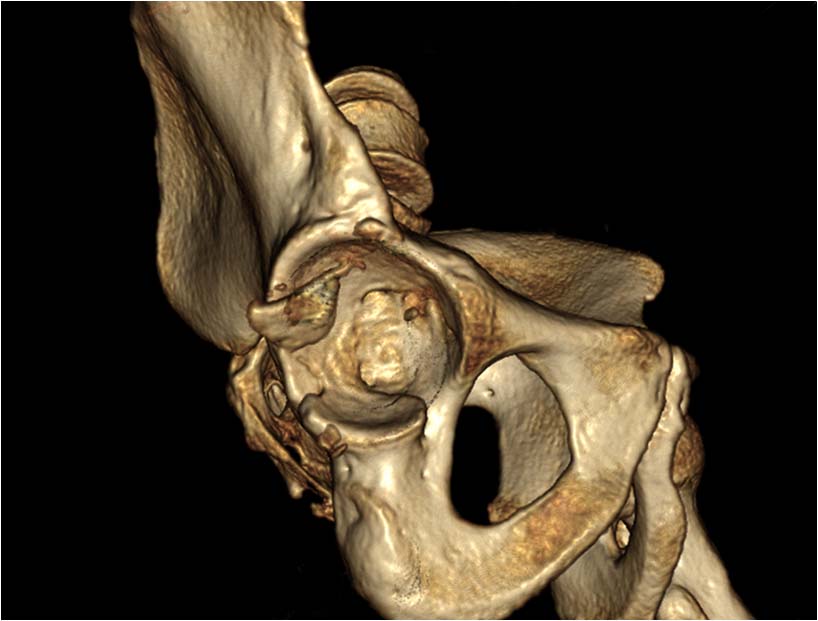

При поступлении выполнено закрытое вправление головки бедра, налажено скелетное вытяжение. Контрольный рентген показал разницу в ширине суставных щелей в сравнении с неповрежденной стороной. Сделали КТ, которое подтвердило наличие внутрисуставного фрагмента задней стенки вертлужной впадины и перелом нижне-медиального сегмента головки со смещением (Pipkin IV).

Через 12 дней выполнен остеосинтез головки 3-мя самокомпрессирующими винтами Герберта. Доступ Kocher-Langenbeck с флип-остеотомией большого вертела и задним хирургическим вывихом головки бедра. Интерпонирующий внутрисуставной фрагмент представлял собой лабрум с тонкой костной пластинкой от заднего края впадины. Фрагмент извлечен и фиксирован техникой spring-plate.

Обращал на себя внимание значительный дефект хряща головки бедра в нагружаемой зоне (как результат контакта головки с внутрисуставным фрагментом). Глубина повреждения хрящевого покрытия в центральной части дефекта достигает кости. Ничего не делали, расчитывая на замещение дефекта фиброзным хрящом. Промыли головку с впадиной, вправили вывих и ушились с активным дренажом.